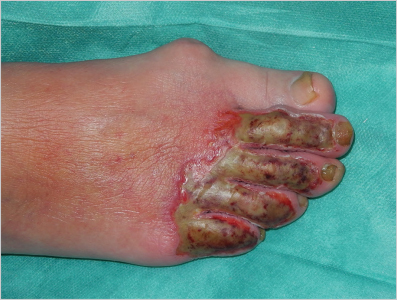

Given that energy transference is rarely homogeneous, different depths within the same lesion are frequently found. Occasionally a gradient of injury is clearly recognized (

Fig. 18.6). On other occasions, a patchy geographic distribution may be seen.